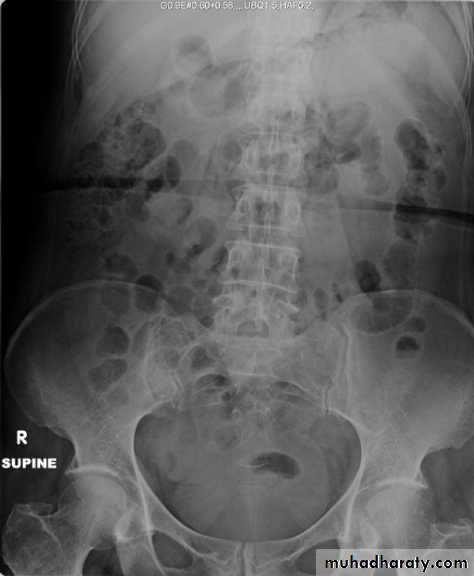

2-Blood urea & serum criatinin 3-radiological:- KUB (kidney,ureter,bladder):-A-BonesSB-Soft tissueC-StonesA plain radiograph of the abdomen and pelvis includes the area above both adrenal glands and extends to 2 cm below the symphysis pubis

KUB: site, skin, sex, stones, psoas shadow, skeleton, and soft tissue shadow